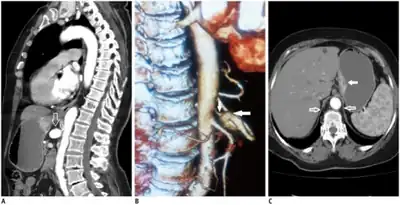

Further evaluation and confirmation can be obtained via angiography to investigate the anatomy of the celiac artery.[5] Historically, conventional angiography was used, although this has been largely replaced by less invasive techniques such as computed tomography (CT) and magnetic resonance (MR) angiography.[2][5] Because it provides better visualization of intra-abdominal structures, CT angiography is preferred to MR angiography in this setting.[5] The findings of focal narrowing of the proximal celiac artery with poststenotic dilatation, indentation on the superior aspect of the celiac artery, and a hook-shaped contour of the celiac artery support a diagnosis of MALS.[2] These imaging features are exaggerated on expiration, even in normal asymptomatic individuals without the syndrome.[2]

Proximal celiac artery stenosis with poststenotic dilatation can be seen in other conditions affecting the celiac artery.[2] The hook-shaped contour of the celiac artery is characteristic of the anatomy in MALS and helps distinguish it from other causes of celiac artery stenosis such as atherosclerosis.[2] This hooked contour is not entirely specific for MALS however, given that 10–24% of normal asymptomatic individuals have this anatomy.[2]

Median arcuate ligament syndrome-a)Stenosis and aneurysm of celiac artery because of compression arrows b)severe stenosis and poststenotic dilatation white arrow c) median arcuate ligaments arrows and gastric mucasal thickening